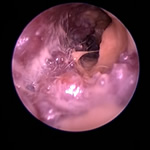

耳ダニ感染後の鼓膜喪失と中耳炎

長く耳ダニに気付かず治療が遅れた猫です。すでに鼓膜を失っており、中耳をきれいに洗浄すると赤い肉芽が確認できました。この肉芽を除去し点耳薬で治療すると改善。鼓膜が全く残っていないため鼓膜の再生は期待できませんが、痛みや痒みもなく元気に過ごしています。